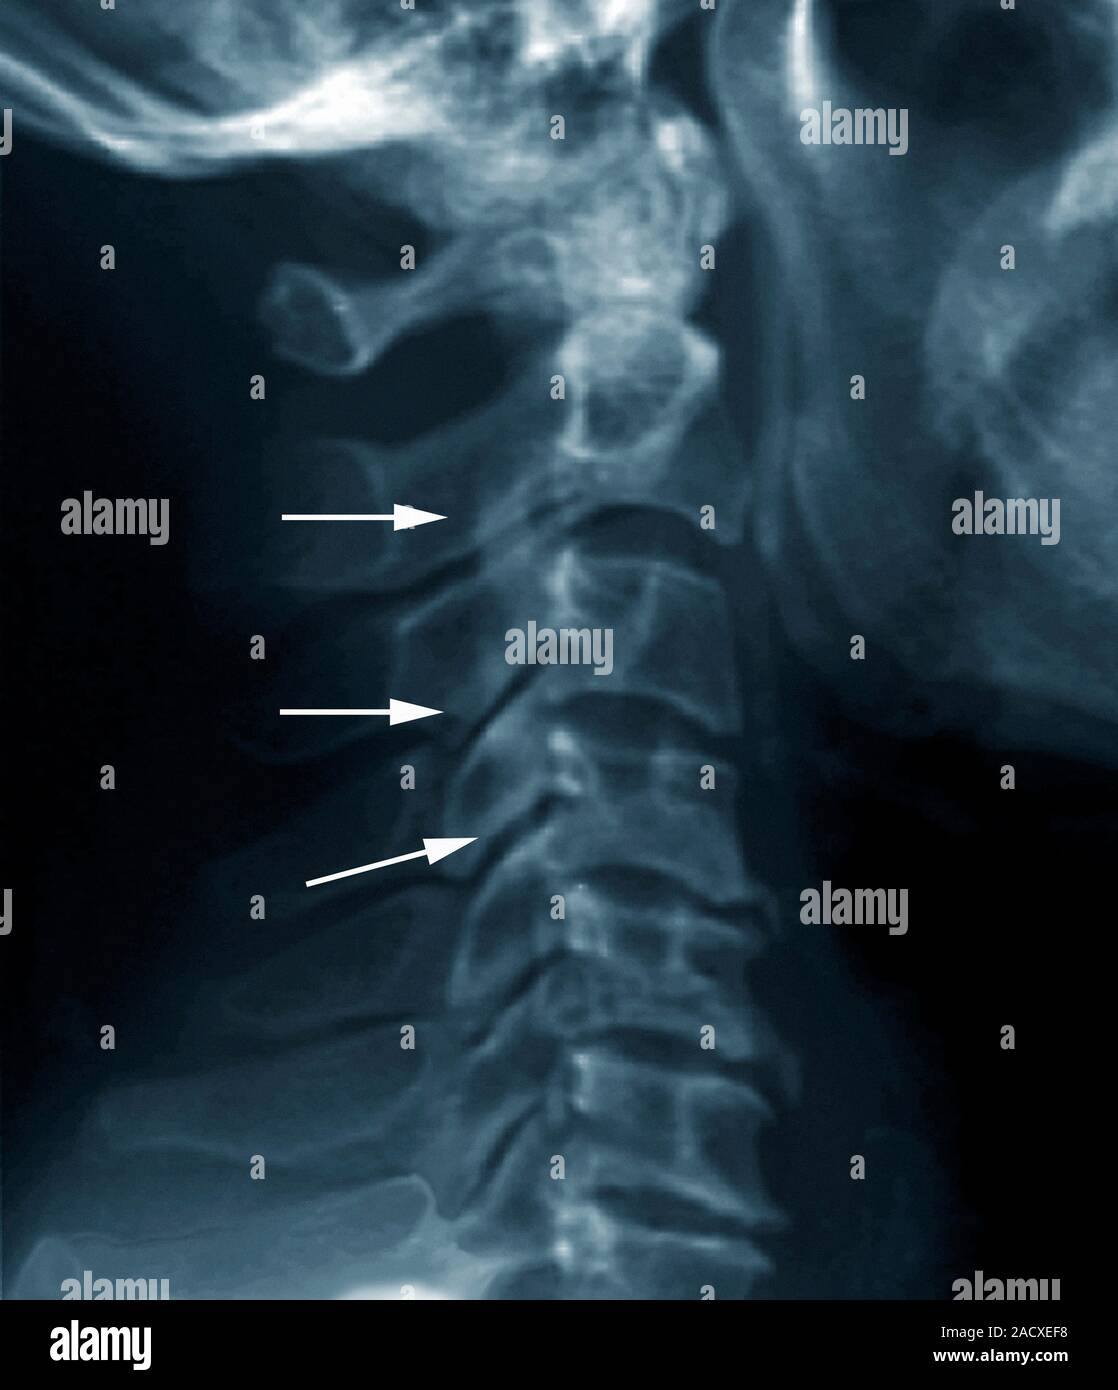

From www.alamy.com

Forestier disease, also known as diffuse idiopathic skeletal Dish Ziekte Van Forestier Dish staat voor ‘diffuse idiopathische skeletale hyperostose’ en wordt ook wel de ziekte van forestier genoemd. De ziekte van forestier is een aandoening waarbij extra bot aangroeit op plaatsen waar pezen of gewrichtsbanden aan het bot hechten. Dish, also known as forestier disease, is a common disorder of unknown etiology characterized by enthesopathy of the. Symptomen, nekwervelimpact, erfelijkheid en beheeradviezen.. Dish Ziekte Van Forestier.

From radiopaedia.org

Image Dish Ziekte Van Forestier Dish is een engelstalige afkorting van: De behandeling van de ziekte van forestier bestaat vaak uit een combinatie van pijnstillers, fysiotherapie en soms, bij voetklachten, uit. De ziekte van forestier is een aandoening waarbij extra bot aangroeit op plaatsen waar pezen of gewrichtsbanden aan het bot hechten. Symptomen, nekwervelimpact, erfelijkheid en beheeradviezen. De ziekte van forestier is is een aandoening. Dish Ziekte Van Forestier.